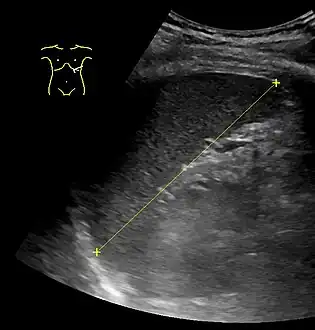

Maximum dimension of the spleen on abdominal ultrasonography

The standard system for classifying splenomegaly on radiography is:[13][14]

- Normal (not splenomegaly): the largest dimension is less than 11 cm

- Moderate splenomegaly: the largest dimension is between 11–20 cm

- Severe splenomegaly: the largest dimension is greater than 20 cm

For children, the cutoffs for splenomegaly are given in this table, when measuring the greatest length of the spleen between its dome and its tip, in the coronal plane through its hilum while breathing quietly.[17]